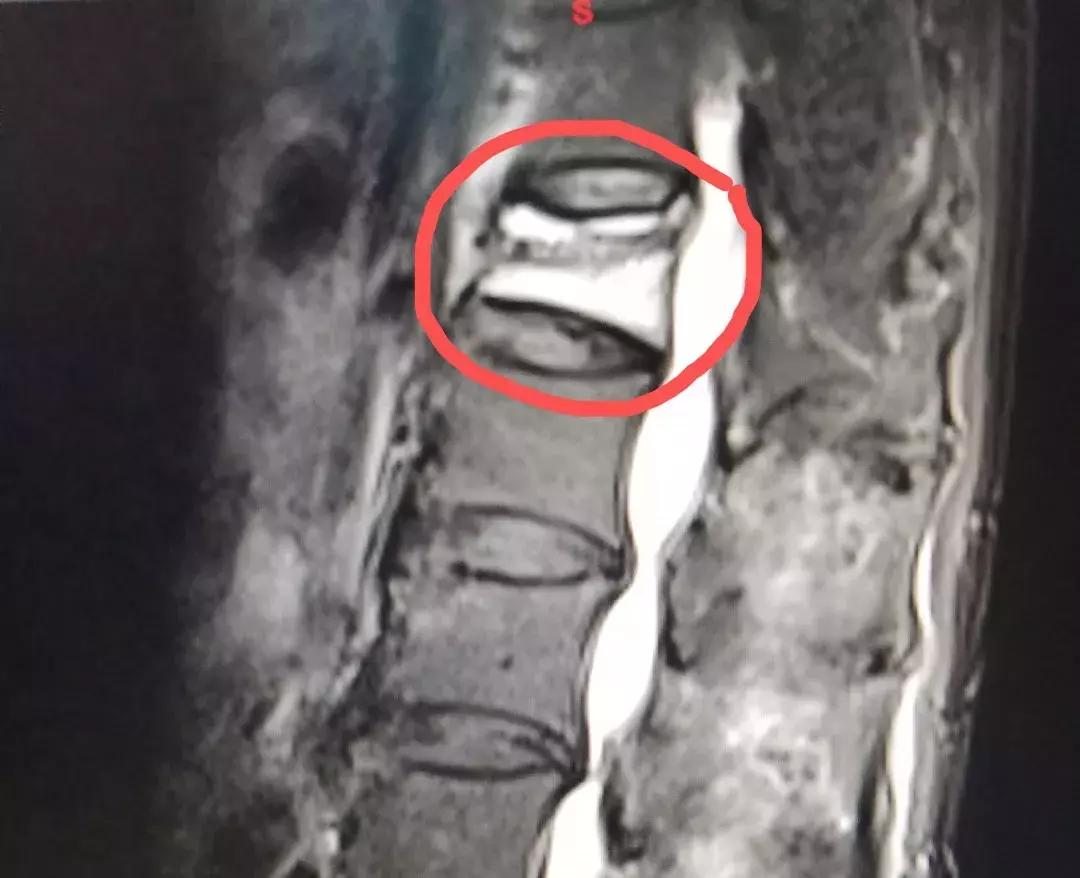

术前影像,红圈内为压缩骨折的椎体

术后影像,红圈内为注入骨水泥后的椎体